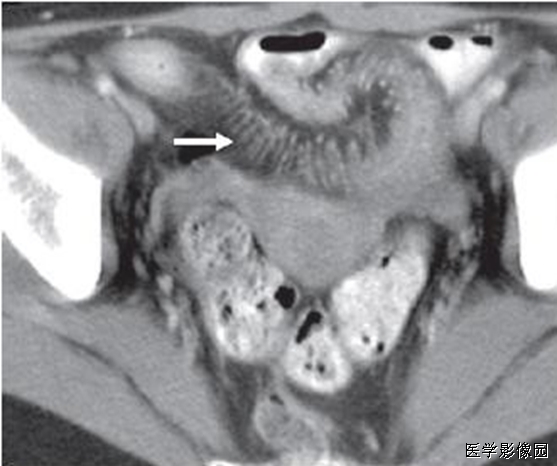

左图:腹部增强CT横扫显示结肠附近高衰减环(箭头)围绕脂肪密度中心。此环为肠脂垂炎症导致外脏层腹膜增厚。

右图:CT显示结肠周围1-4cm的脂肪密度团块周围2-3mm高衰减环。偶尔有高衰减中心,此为栓塞的血管及出血坏死。

结肠旁与结肠壁相连肿块,近似于乳腺密度,中心密度较低,边缘密度较高,邻近脂肪间隙模糊,局部腹膜增厚